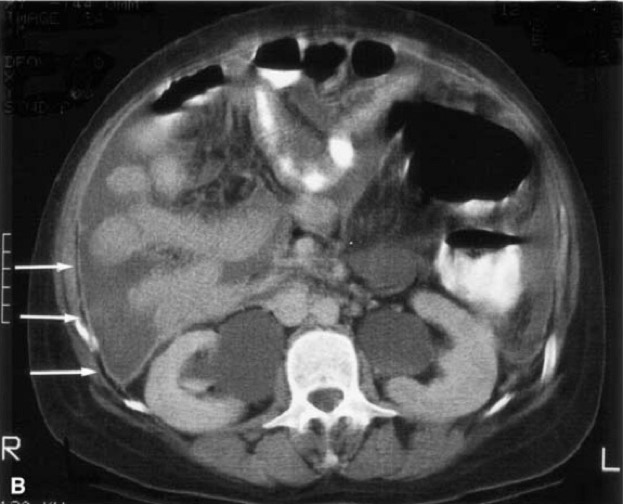

1. Lymph Nodes

- Bulky large, soft tissue attenuation with uncommon necrosis

- Size >3cm – to differentiate from mycobacteria

- Encasement of vessels